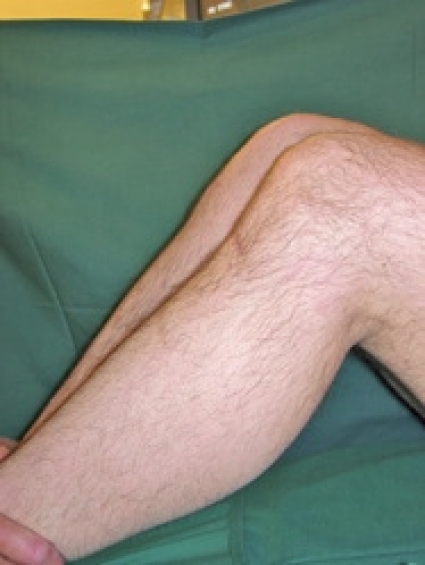

Inspektion. En synlig svullnad i ett knä indikerar ökad risk för omfattande skada. Förekomst av sår och exkoriationer tyder på direktvåld och kan ha betydelse för den fortsatta utredningen i form av ökad risk för infektion vid punktion och artroskopi. Synliga felställningar tyder på fraktur eller luxation. Patellaluxationer har dock oftast spontanreponerats vid ankomst till sjukhuset.

Vid patellaluxation finns ofta en diffus ömhet över mediala patellaretinaklet men ännu oftare en distinkt ömhet över mediala femurepikondylen, där mediala patellofemorala ligamentet fäster. En inslagen menisk ger ofta distinkt palpationsömhet över främre delen av ledspringan.